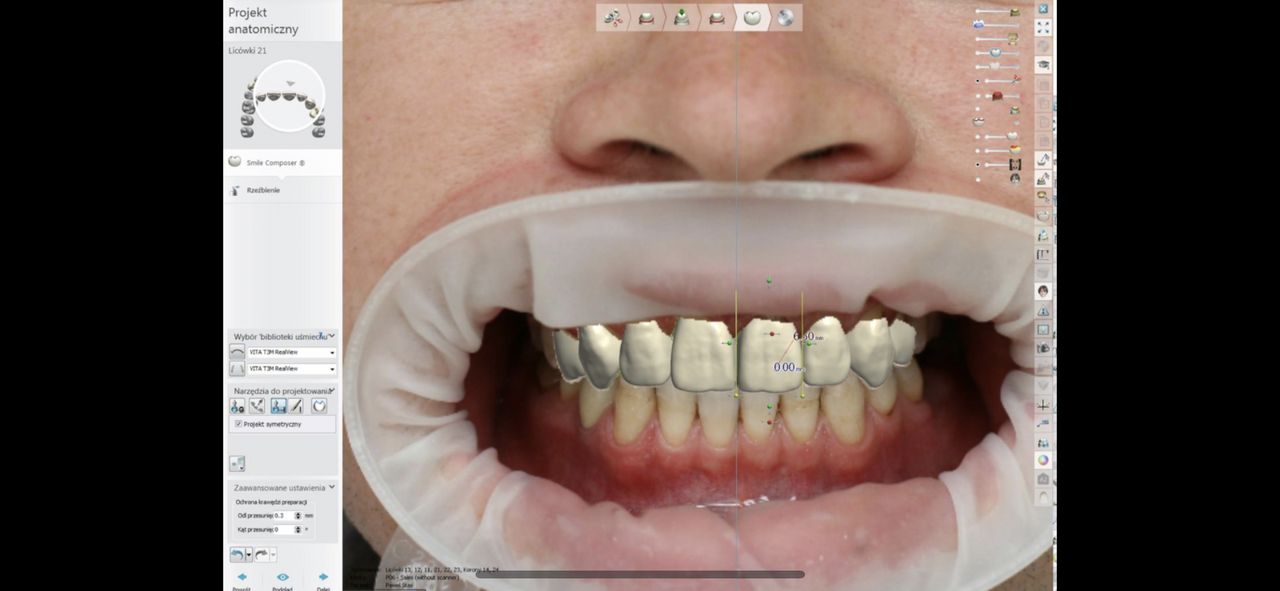

Ukończyłem Łódzką Akademie Medyczna, na wydziale stomatologicznym . W 2007 roku uzyskałem tytuł specjalisty w dziedzinie protetyki stomatologicznej. Regularnie pogłębiam wiedze z zakresu stomatologii o czym świadczą zdobyte przeze mnie certyfikaty . W chwili obecnej prowadzę NZOZ Duodent , specjalistyczny gabinet protetyczny na Widzewie - wschodzie , przy ul. Gogola 12 . Znajdują sie tu trzy nowocześnie urządzone i wyposażone gabinety stomatologiczne. Pracujemy na sprzęcie Sterna Webera, prestiżowej szwajcarskiej firmy produkującej unity stomatologiczne...W gabinecie znajduje sie skaner wewnątrzustny MEDIR i 500 R , gdyz obecnie gabinet nasz wyspecjalizował sie w PROTETYCE CYFROWEJ

Współpracujemy z cyfrowa pracownia techniczna z Warszawy - SCAN LAB.

. W tym wypadku odległość nie ma znaczenia , gdyż wyciski w formie cyfrowej trafiają internetem do pracowni w ciągu paru sekund po ich uzyskaniu drogą skanowania w ustach pacjenta, bez zniekształceń i deformacji. CAD/CAM to supernowoczesna frezarka komputerowa, wycinająca z bloczku cyrkonu najbardziej precyzyjne elementy .